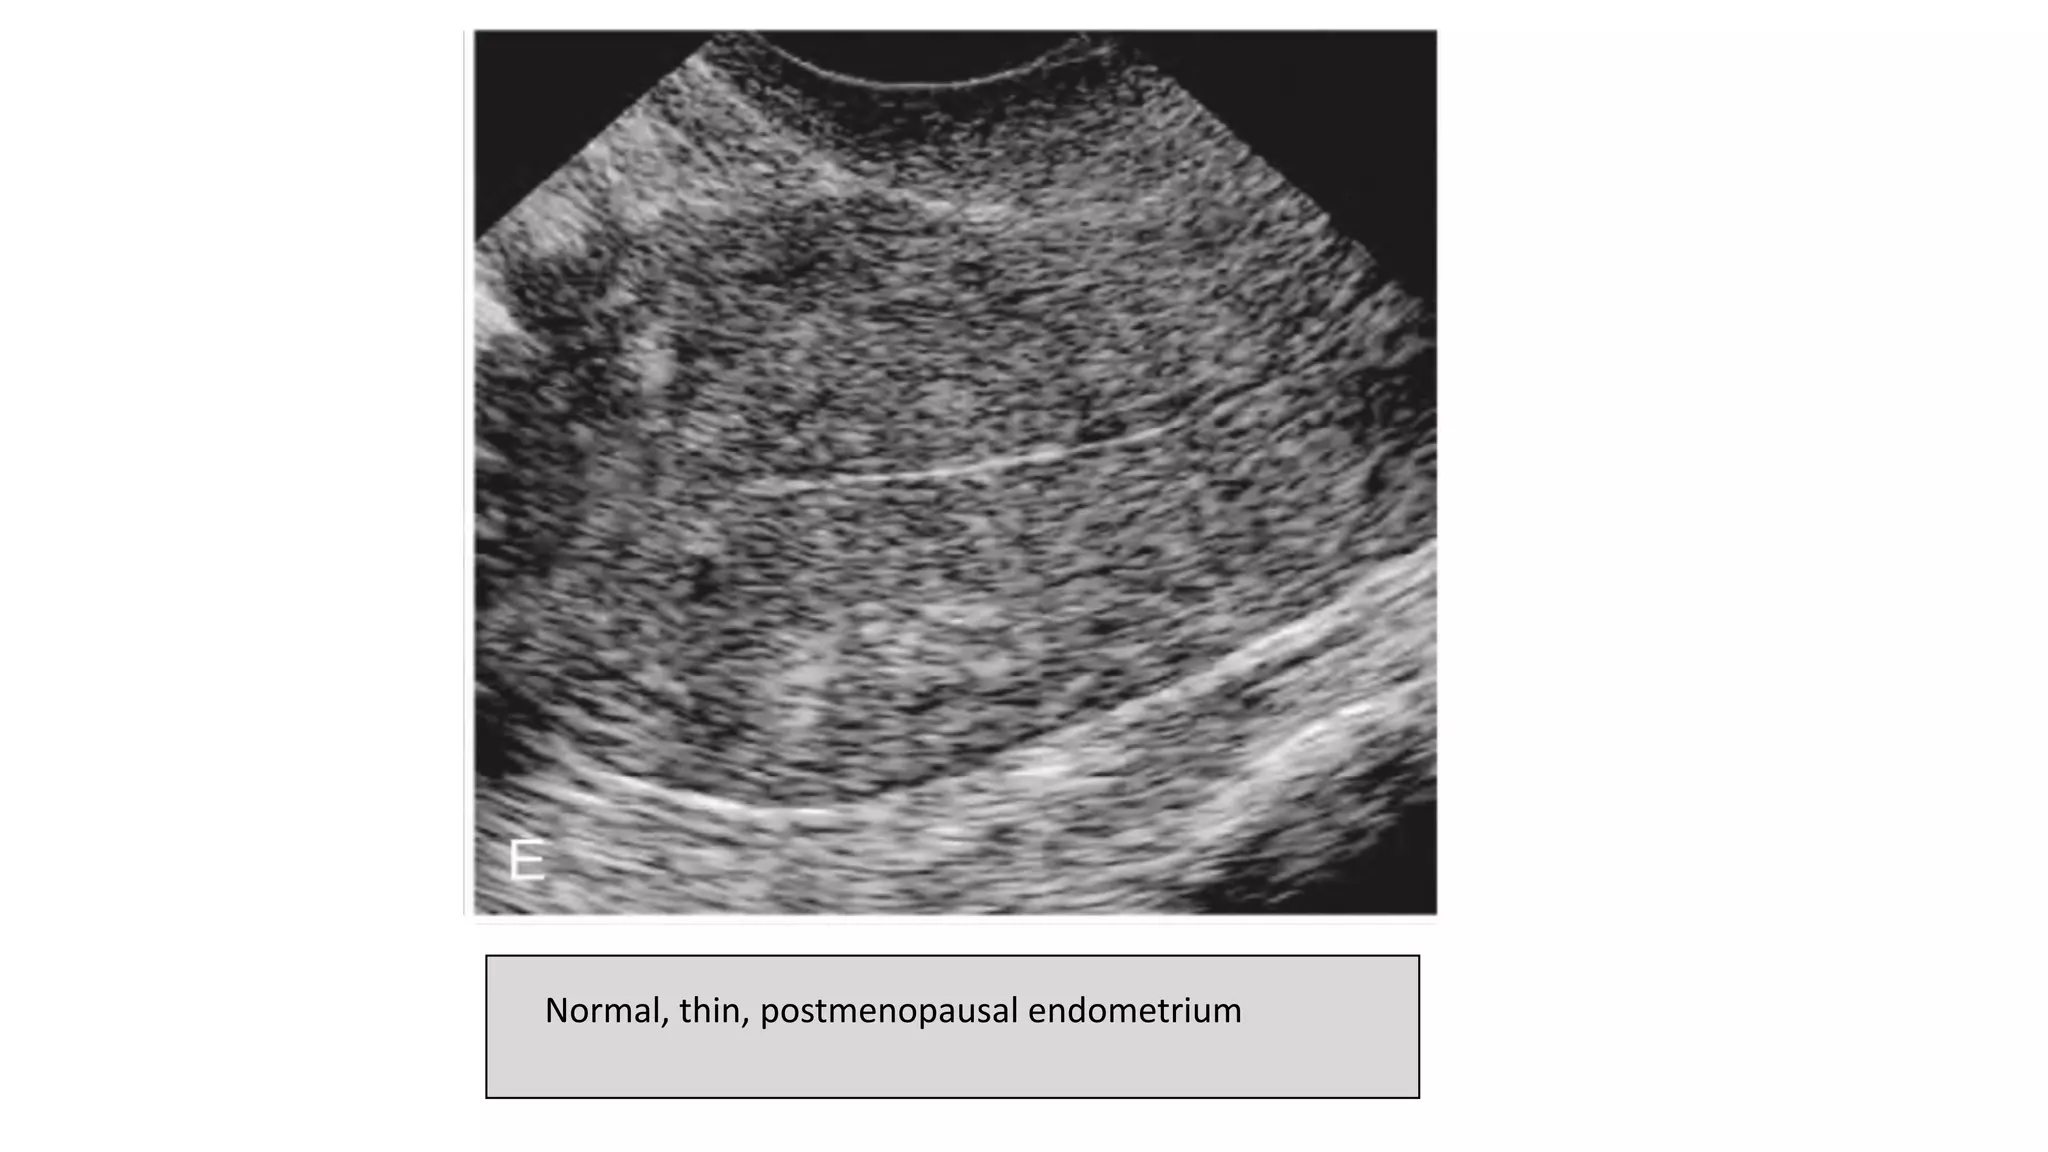

Normal, thin, postmenopausal endometrium

POSTMENOPAUSAL ENDOMETRIUM

• Postmenopausal Endometrium should be

thin, homogeneous, and echogenic.

• Homogeneous, smooth endometria

measuring 5 mm or less are considered

within the normal range with or without

hormonal replacement therapy.